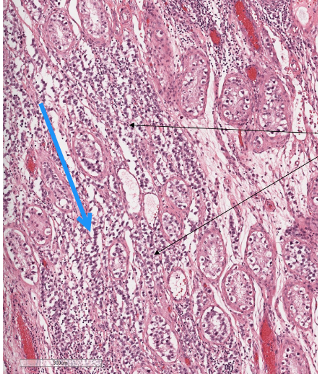

What is shown here?

Testis

Lot of abnormal cells

Infiltration of lymphocytes

Blood vessels

Little bit of invasion of normal testicular structure